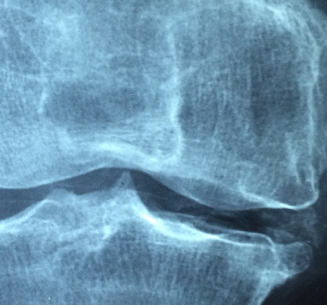

최근 다리 관절이 안 좋아져 집 앞을 걷다 말고 정형외과를 급하게 찾아간 적이 있습니다. X-Ray와 초음파 사진을 찍어 진단을 봤고 별 증상 없이 근육이 놀래었다는 진단을 받았습니다. 2주 뒤에도 통증이 계속되어 동네 다른 병원을 수소문하여 정형외과를 찾아갔고 인대 파열이라는 진단을 받았습니다.

관절 파열 정형외과